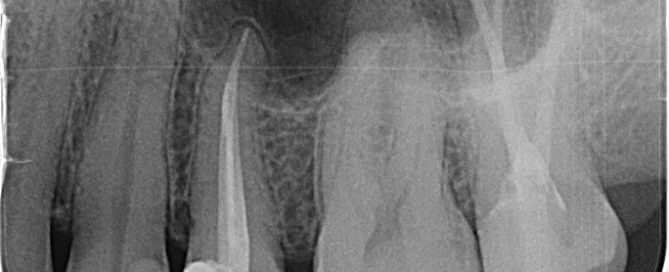

Wurzelbehandlung – Endodontologie